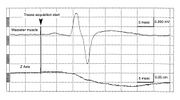

| 22:58, 15 July 2024 | Siro e jaw jerk 2.jpg (file) |  |

736 KB | Gianni | 2 | |

| 22:58, 15 July 2024 | Sirignathograph e jaw jerk 1.jpg (file) |  |

707 KB | Gianni | 2 | |